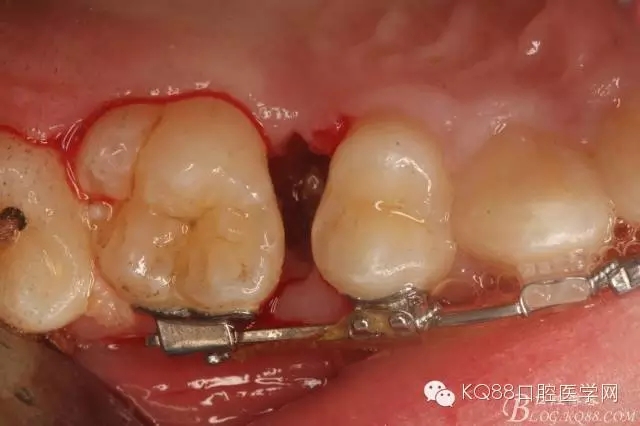

圖8.因16與14合面的間隙僅2mm左右,牙根無法合向脫位,如何考慮15牙根的脫位將是最大問題。高速手機(jī)去除牙間隙內(nèi)的覆蓋在15牙根表面的牙齦組織

圖10.去除牙齦組織后。露出15牙根斷面,合面無法脫位